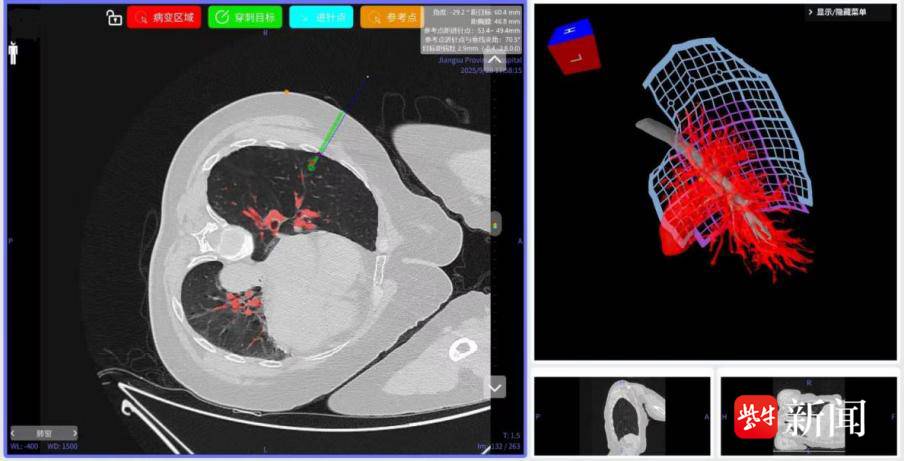

但在陈亮主任团队的细致评估与方案打磨下,患者张阿姨(化名)的手术从一开始就走上了“不一样的快车道”。术前,陈亮教授团队联合技术支持团队将张阿姨的CT影像导入专用系统,软件如同“智能绘图师”,瞬间自动生成一份肺部“全景导航图”——结节的大小、藏在肺部的具体位置,支气管蜿蜒的走向,肋骨与血管密密麻麻的分布,所有关键结构都清晰得像“标注好的地图”,相当于提前给手术团队画好了精准路线,彻底跟传统“凭经验盲穿”的不确定性说再见。

60 岁女性,右肺中叶结节定位前规划

病人麻醉后,潘相龙医生戴上AR眼镜,目光聚焦患者的病灶区域,通过调整视角找准结节位置,手持定位针,并循着导航提示的“最优路径”,稳稳将一枚“伞形”标记物送到结节旁并释放——整个过程像 “精准打靶”,巧妙避开了肋骨和血管,全程流畅又安全。

AI与AR技术的“强强联手”,还让张阿姨胸部器官的“数字孪生体”以3D形式实时呈现在潘医生眼前,这一画面同时通过电脑屏幕同步给团队其他成员,大家 “同看一张精准图”,最终,定位过程仅用了不到10分钟,效率大幅提升。随后,陈亮主任团队按照术前3D-CTBA规划的方案,顺利为张阿姨实施荧光胸腔镜右肺S4a单亚段切除术——不仅精准定位、“清除”了肺结节,更最大限度保留了正常肺组织,为她术后快速恢复、维持良好肺功能打下了坚实基础。

术前 3D-CTBA 规划